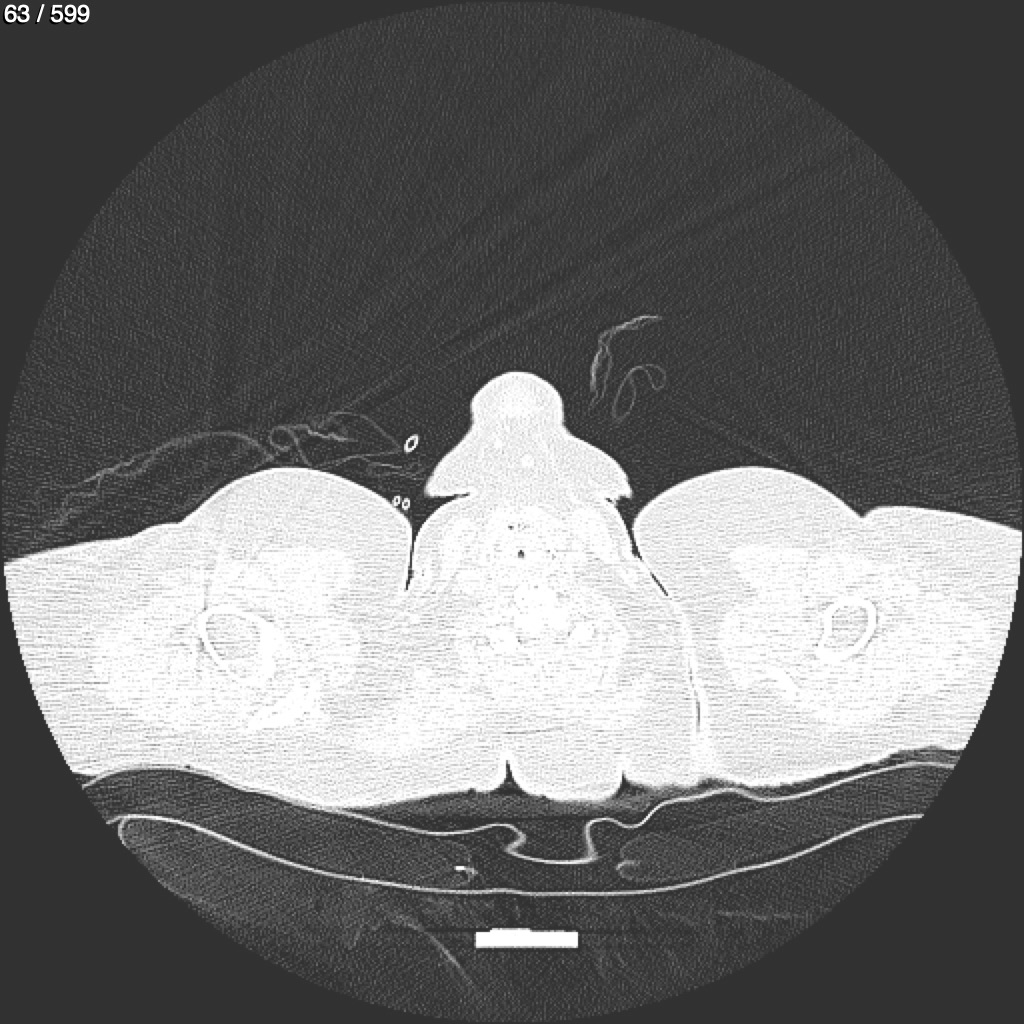

Home G​l​o​r​i​a​ ​G​l​a​d​y​s​ ​B​e​a​s​l​e​y​ ​-​ ​T​ó​r​a​x​ ​T​o​r​a​x​_​S​i​m​p​l​e​ ​(​A​d​u​l​t​o​)